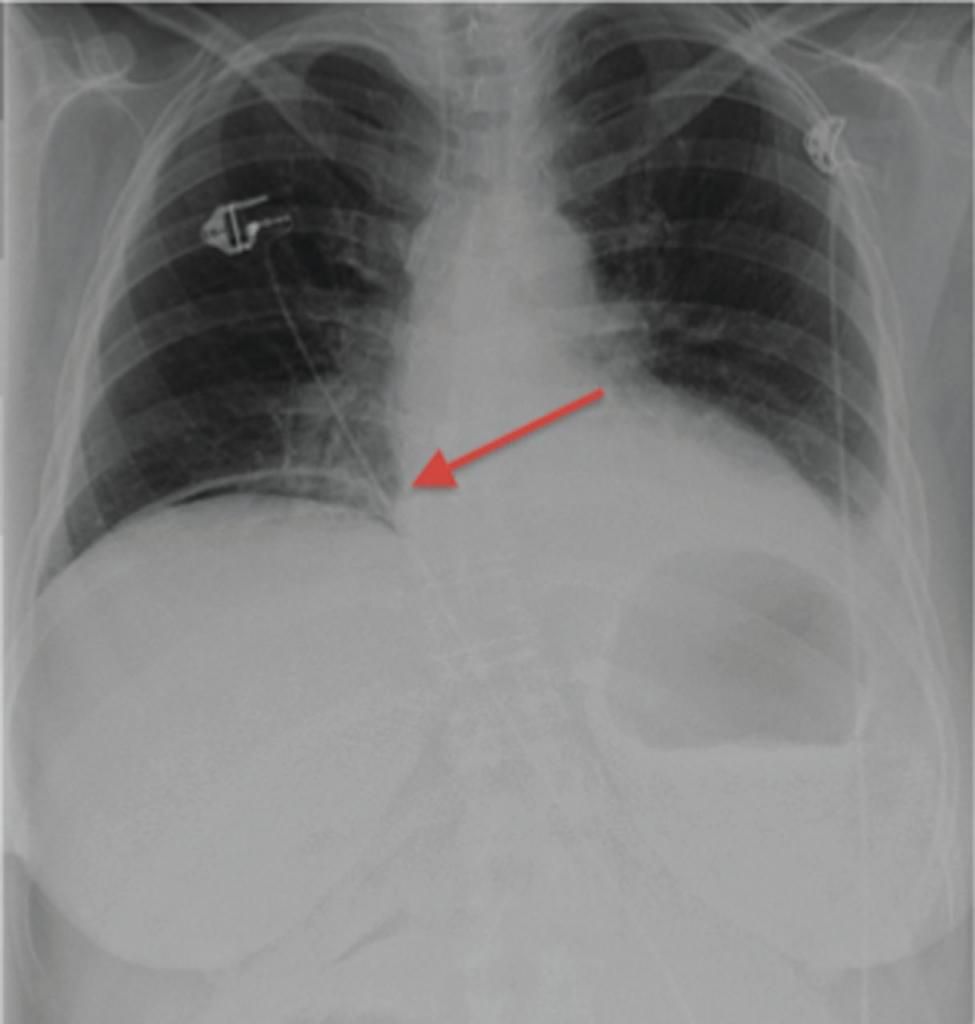

CT scan of the chest: abscess formation in the right lower lobe …

Pulmonary abscess | Radiology Case | Radiopaedia.org